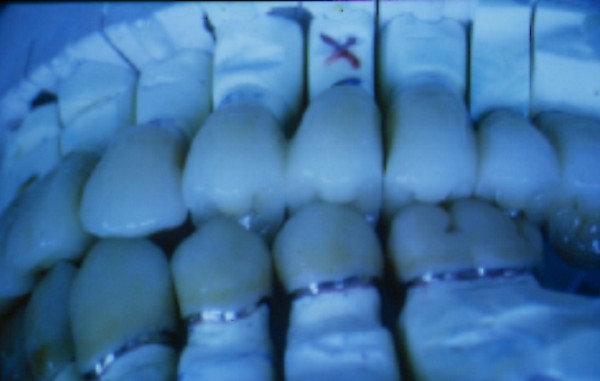

RESUMEN Más allá en el tiempo, respecto de las razones más frecuentes de fracasos como temperatura de fresado, infecciones, falta de fijación inicial, falta de higiene, etc., la OCLUSIÓN recibe sobre sí, la responsabilidad de la permanencia de la osteointegración, como así de la ortofunción del sistema todo. Sometimes ago,conserning the most frecuent reason of failures such as the strawberry action temperature, infections and lack of hygiene…etc.,the OCLUSION has itself the responsability af having the osteointegration well as the allsistem ortofunction . DESARROLLO La valoración de los fracasos en IMPLANTOLOGÍA es difícil de contabilizar sobre todo después del año, ya que el confort logrado por lo general, hace que el paciente realice correctamente sus primeros controles, y después; apoyado en su bienestar; intente subconscientemente olvidar ese período de su vida, que si bien le devolvió su capacidad masticatoria, fonética, social, etc., le ocasionara gastos, molestias, sufrimientos. … la APLICACIÓN de dichas fuerzas, requiere de una exactitud mucho mayor. Los esquemas propuestos a través de los años, no son muchos ni muy variados… I-Evitar las fuerzas tangenciales. II-Repartir las fuerzas lo máximo posible. Sin embargo, muchas veces se confunden los conceptos anteriores con criterios inexactos. Por ej: a-Reducción de las caras vestibulares y palatinas, aceptando que la menor superficie de intercontactos reduce la carga. b-Utilización de la Función de Grupo Posterior, en la creencia de que repartiendo el esfuerzo en las piezas posteriores, ganamos resistencia; a la potencia ejercida por los músculos. c-No permitiendo el contacto excéntrico de un canino implantado, para aliviarlo de las cargas laterales, sobre cargando de esta manera la tabla premolar-molar en el Lado de Trabajo. Algunos conceptos aislados, que forman parte de toda una filosofía de la Oclusión (OCLUSIÓN ORGÁNICA), sean tal vez de ayuda para echar luz sobre los preceptos anteriores. 1º-PROPORCIONES FUNCIONALES DE UN PAR OCLUSAL En la figura siguiente, observamos la relación final masticatoria de un PAR OCLUSAL: En el se ven los contactos puntiformes, producto del choque de superficies redondeadas contra superficies redondeadas («Solo pueden encontrarse en un punto» Ref: Principios Mecánicos Esferoidales.W.Mc.Horris.) Si Miramos con atención este tipo de contactos interoclusales, veremos que la superficie actuante es mucho menor que la superficie total de la cara oclusal: 45% (Fig.1) Por lo tanto, si no es por razones del Pilar de Emergencia para no crear un espacio biológico inadecuado… ¿POR QUÉ REDUCIR LA CARA OCLUSAL VESTÍBULO LINGUALMENTE? (Figs. 2-3-4-5) Si observamos con atención las figuras 2-3-4-5, veremos desde todos los planos , que el área contactante es muy reducida respecto del ancho oclusal total, siendo las fuerzas resultantes , AXIALES al eje implantario. 2º-FUNCIÓN DE GRUPO POSTERIOR. FUNCIÓN CANINA. Tres son las razones por las cuales nos inclinamos a la utilización de la Función Canina. En cambio, en el esquema de FUNCIÓN CANINA, podemos observar que el BRAZO DE POTENCIA, es prácticamente igual al de RESISTENCIA, equilibrando de esta manera la palanca y destruyendo mucho menos las estructuras de soporte(Interface I-H) (Fig. 7) Otra de las razones de peso en este tema es la DIFERENCIA DE ANGULACIÓN que existe entre la cara palatina del canino y las vertientes contactantes del sector premolar-molar. A MAYOR ANGULACIÓN, MENORES FUERZAS LATERALES(Perpendiculares al Plano), y por lo tanto , menor destrucción de la interface Hueso-Implante(Figs. 9-11). DIFERENCIAS EXCITATORIAS DE LOS GRUPOS MUSCULARES. Por último debemos considerar que el intercontacto dentario del sector anterior, estimula excitatoriamente a las fibras anteriores y verticales del temporal (Figs.12-13-14-15), mientras que los contactos posteriores lo hacen con la cincha pterigo-maseterina(Fig. 16-17-18-19) Por lo tanto ,si se comprende el fisiologismo de estos conceptos, es sencillo entender que la sobrecarga de los sectores posteriores es nocivo generando fuerzas tangenciales de Alto Potencial Patológico. 3º-FUNCIÓN DE GRUPO ANTERIOR Las ventajas de un Brazo de Resistencia mayor se acentúan cuando tenemos el esquema de FUNCIÓN DE GRUPO ANTERIOR. Además, debemos tener en cuenta que, durante la función de un Ciclo Masticatorio, es más importante la Desoclusión Final que la Desoclusión Inicial, ya que al ser más larga esta última, es durante el transcurso de su deslizamiento cuando se ejercen fuerzas laterales mayores(Fig. 21) A medida que la punta del canino inferior se acerca a la O.R.C., o sea al Punto de Contacto Intercanino, las fuerzas laterales disminuyen en virtud del acortamiento del brazo de potencia de la palanca, hasta que, al terminar su recorrido, la fuerza es proyectada axialmente sobre el eje del canino superior, debido a que, al margen de la intensidad que la fuerza trae durante el cierre, la dirección de la misma «apunta» en esa dirección. Por eso decimos que los caninos Axializan el Ciclo Masticatorio. Si estamos imitando en lo posible a la naturaleza, no olvidemos este detalle que los dientes naturales provéen, para evitar las fuerzas laterales del canino a la hora de realizar la supraestructura coronaria del mismo. Es ahora menester acentuar que la problemática concreta se manifiesta, no durante la función, sino durante la PARAFUNCIÓN… Cuando estudiamos recorridos de la Dinámica Mandibular, desde el conocido Bicuspoide de Posselt hasta cualquiera de los registros pantográficos, estamos invirtiendo la dirección del movimiento… A.- El primer premolar es el más anterior de la tabla oclusal posterior. Por lo tanto el brazo de resistencia es el mayor de dicha tabla. B.- El lateral, como parte del grupo anterior, cuenta con un empotramiento tipo «clavo largo», y el interseptum lateral -canino, que se opone a la fuerza, es mucho más grueso que la tabla vestibular del primer premolar(Fig.23) C.- Condiciones, las dos anteriores que se favorecen considerablemente, si al enfundar el lateral se logra junto al central una Función de Grupo Anterior. D.- De manera más artificiosa, la instalación de una placa de relajación, soluciona durante la noche lo nocivo de las fuerzas laterales. Veamos un par de casos, como ejemplo de lo dicho: Paciente de 54 años que se presenta a la consulta portando prótesis completa superior y antagonista natural que soporta fundas de porcelana. Obsérvese la función de grupo posterior ejercida, y las consecuencias de la misma: Otro paciente que presenta fractura de la cúspide fundamental de un onlay de porcelana antagonista de cinco piezas implantadas (Fig.27). Radiográficamente se observa la desinserción de uno de sus abuttments cementados (Fig.28). En el Lado de Trabajo (LT), no existe el canino encargado de desocluir la zona afectada (Figs.29-30) Como corolario, cabe entonces una pregunta: ¿Es el Implante en el canino quien debe preservar de patología oclusal al resto del sistema…. ¿Es el Implante…un medio…o un fín? BIBLIOGRAFÍA 1- Dibujos tomados del libro del mismo autor: «OCLUSIÓN ORGÁNICA… UN CAMINO HACIA LA REHABILITACIÓN ORAL»(en preparación) 2- «NEUROFISIOLOGÍA DE LA OCLUSIÓN» 3- «OCLUSIÓN Y FUNCIÓN» 4- «FUNDAMENTOS, TÉCNICAS Y CLÍNICA EN REHABILITACIÓN BUCAL» 5- «OCLUSIÓN Y REHABILITACIÓN» 6- «DISFUNCIÓN TEMPOROMANDIBULAR» 7- «PROCEDIMIENTOS CLÍNICOS Y DE LABORATORIO DE OCLUSIÓN ORGÁNICA» 8- «ESTUDIO ELECTRÓNICO DEL MOVIMIENTO MANDIBULAR» 9- «OCLUSIÓN: CONCEPTO PARA EL CLÍNICO» 10- «IMPLANTOLOGÍA CONTEMPORÁNEA» 11- «OCLUSIÓN Y DIAGNÓSTICO EN REHABILITACIÓN ORAL» 12- «PRINCIPIOS DE OCLUSIÓN»